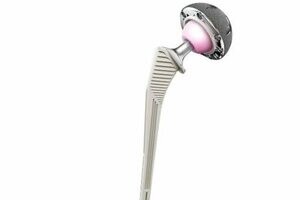

Total hip replacement